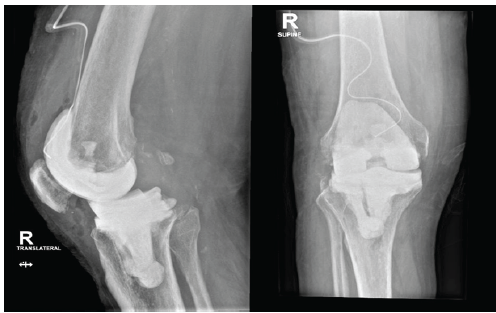

The patient was a 68-year-old male who had been diagnosed with type 2 diabetes, hypertension, and left leg peripheral arterial disease after a stent procedure in the left femoral artery. He first showed an infected left total knee prosthesis (Fig. 1).

Figure 1. Left knee after total knee arthroplasty. Anteroposterior and lateral radiographs demonstrating the left knee following primary total knee arthroplasty prior to the onset of infection.